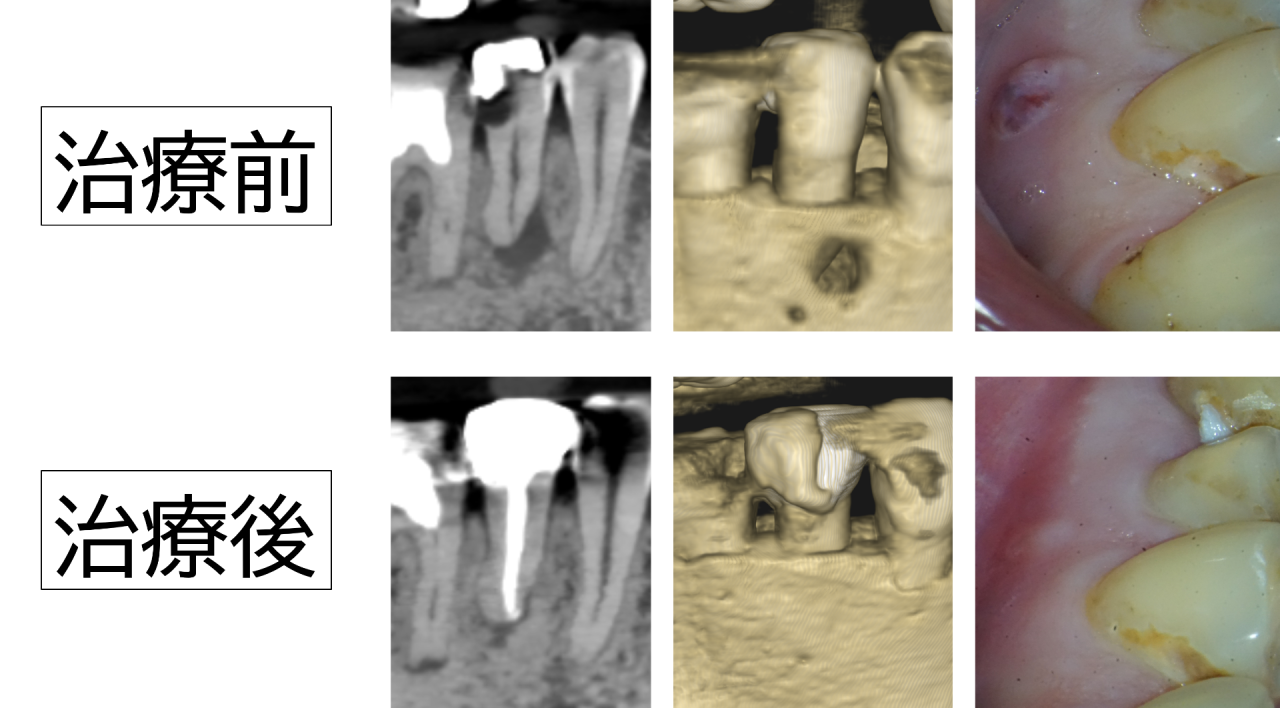

診察すると、過去に装着された銀歯が硬く、長年の噛み合わせによって歯の一部に細かいヒビや欠けが生じていました。その微細な隙間から虫歯菌が入り込み、二次的な虫歯が進行。レントゲン検査では虫歯が神経まで達し、歯の根の先端付近で炎症により顎の骨が大きく吸収している像が確認されました。いわゆる「骨が溶けている」状態です。感覚検査でも温刺激で強い痛みが長く続き、不可逆性歯髄炎の典型的な所見でした。歯ぐきにはできものもできており、骨が突き破られるほど進行していました。

処置後は数日間、噛むと軽い違和感がありましたが、次第に改善。再診時には自発痛もなく、普通に食事ができるようになりました。

治療から半年後のレントゲンでは根の先の炎症が落ち着き、吸収していた顎の骨が徐々に再生していることを確認できました。感染源を取り除いたことで体の自然な治癒が進み、骨が回復してきたと考えられます。